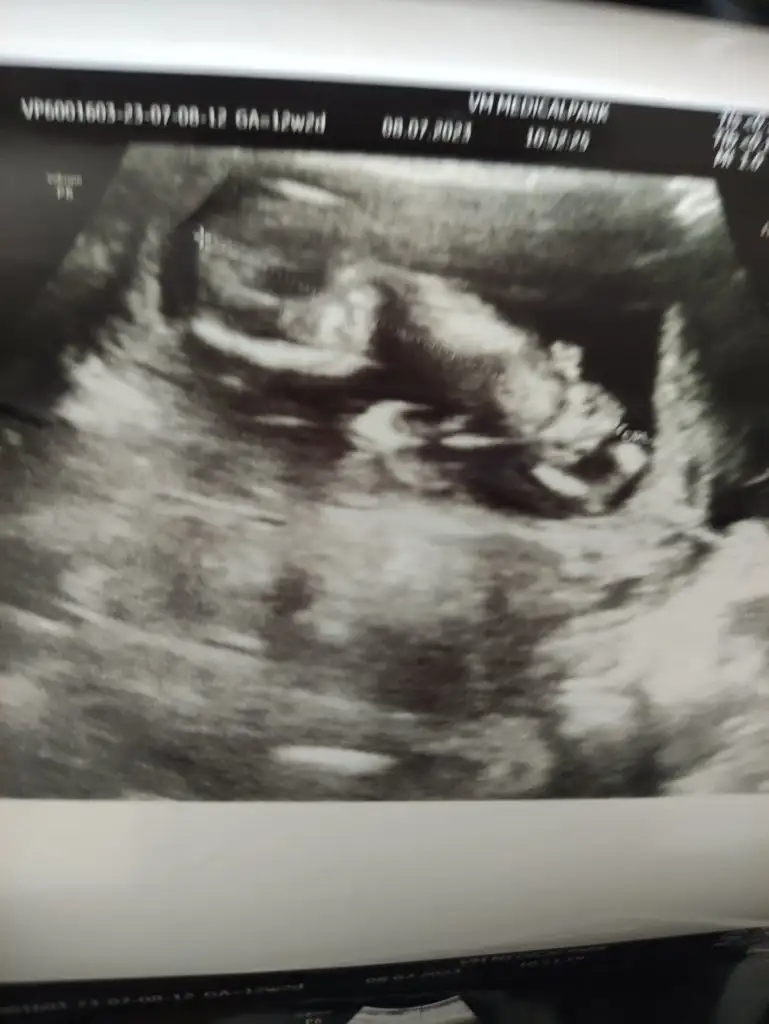

Gebeliklerd3 oluyor bende tansiyon düşüklüğü 6 ya kadar düşerTansiyonunu ölçtün mü, benim de baş ağrım var ama normalde migrenim de var hamileyken daha fazla etkiliyor. Hamilelikte düşük tansiyon iyi diye biliyorum ama hayatı felç edecek duzeydeyse doktoruna bı mesaj at istersen.